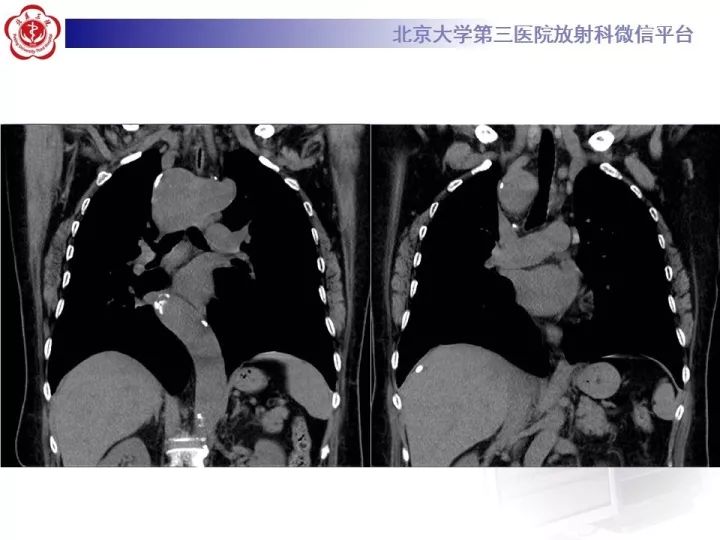

【病例】右位主动脉弓合并迷走左锁骨下动脉1例CT